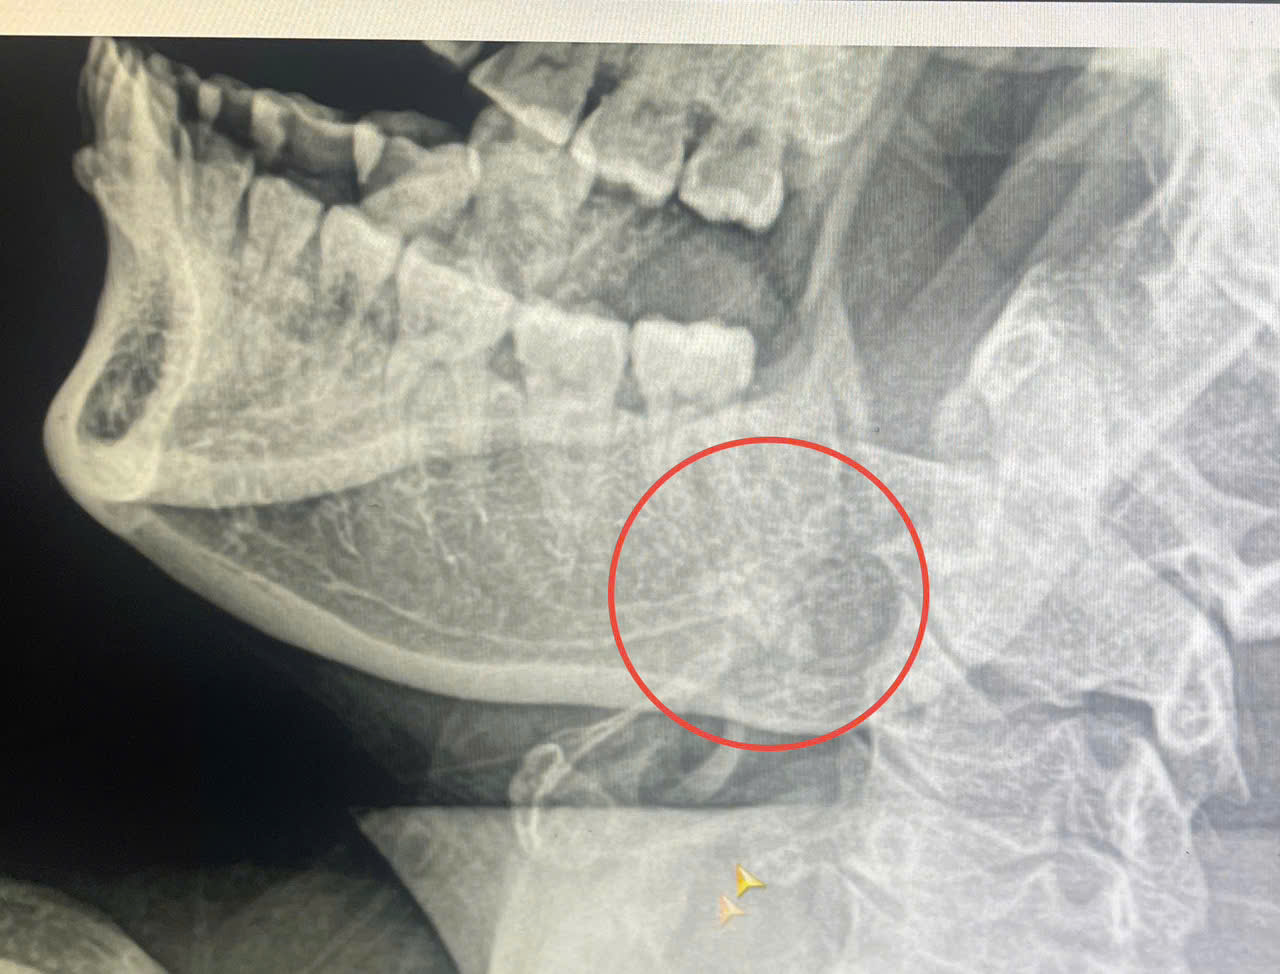

Qua thăm khám và chỉ định cận lâm sàng, các bác sĩ chẩn đoán bệnh nhân bị sỏi ống Wharton tuyến nước bọt dưới hàm trái – một nguyên nhân thường gây tắc nghẽn, viêm đau tuyến nước bọt nếu không được xử lý kịp thời. Qua hội chẩn, bệnh nhân được chỉ định phẫu thuật.

Nhiều sỏi được gắp ra tại tuyến dưới hàm trái của BN

Ca phẫu thuật được tiến hành nhanh chóng. Trong quá trình phẫu thuật, các bác sĩ kiểm tra thấy bệnh nhân có khối cứng di động tại tuyến dưới hàm trái. Tiến hành rạch niêm mạc miệng, đưa dụng cụ chuyên dụng kiểm tra và gắp thành công nhiều viên sỏi ra khỏi ống tuyến.